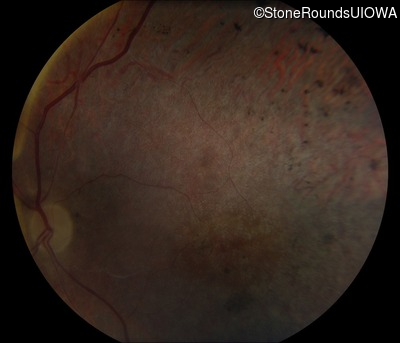

This 41 year old man first came to medical attention at age 18 months when exotropia and amblyopia of his right eye were discovered. At age 11 vitreous strands and retinal vascular sheathing were seen. He has had poor night vision and constricted visual fields since his late teens. Later, at age 44 a traction retinal detachment was noted in his left eye and was treated with a scleral buckle.

Age at visit: 41 years